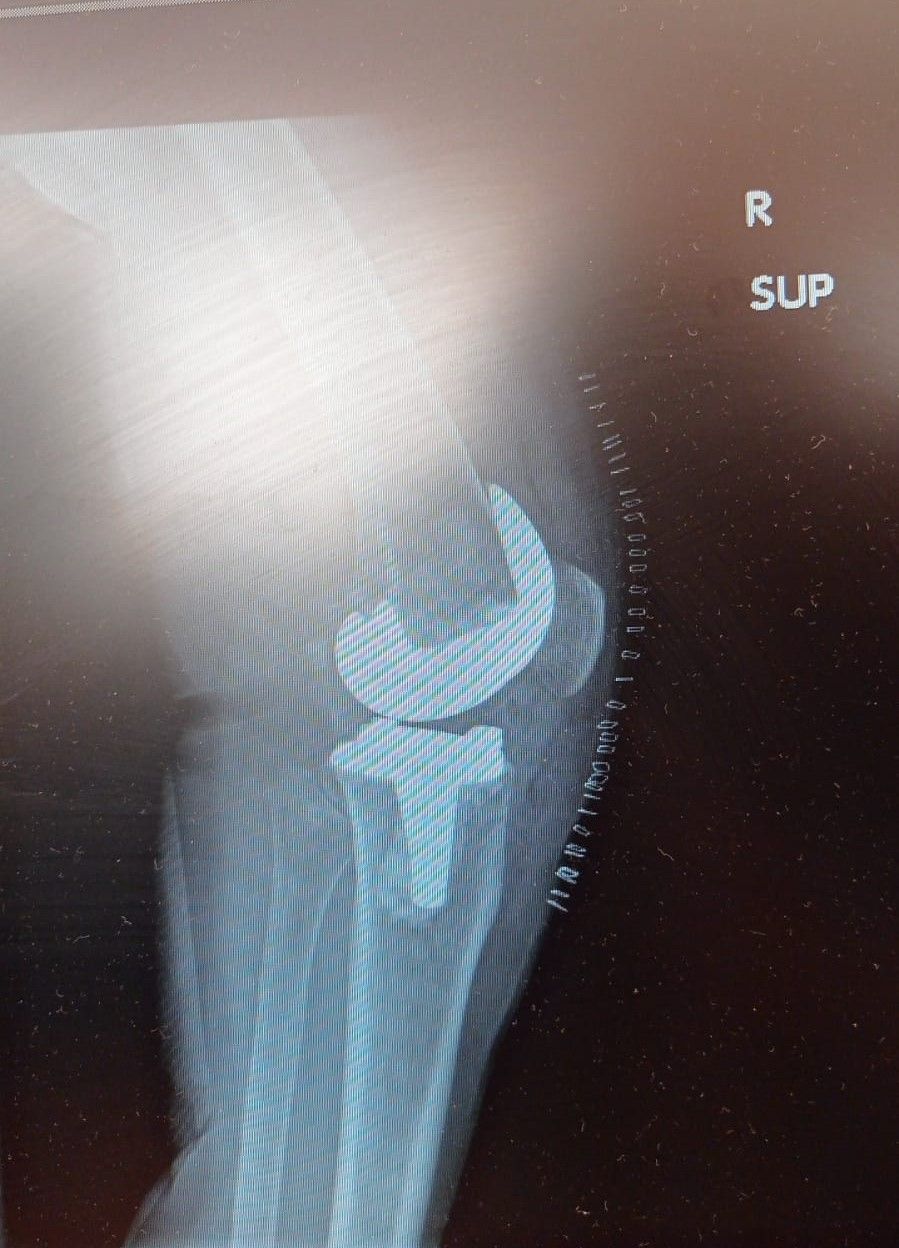

La protesi di ginocchio è costituita da una componente tibiale, una femorale, entrambe in lega di cromo-cobalto, ed un inserto in polietilene che aumenta la congruenza articolare e la stabilità dell’impianto protesico. In genere, le componenti protesiche si fissano all’osso con il cemento, oppure utilizzando degli impianti in tantalio, materiale che si osteointegra completamente entro 3 mesi, senza necessità di cementare.